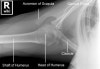

2. Shoulder Ossification center

- Shoulder SI view